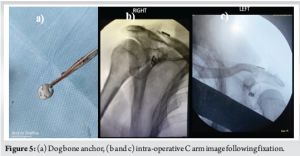

After exposing the coracoid process and the lateral end of the clavicle, a 3.2 mm drill hole was created in both the clavicle and the base of the coracoid process. A guide wire was then passed through, followed by the use of a 3.2 mm cannulated reamer. A Beath pin was inserted to confirm that the tunnel was sufficiently large to accommodate the endobutton and fiber tape (Fig. 3). The beath pin was removed, and the suture material was carefully threaded through the clavicle and into the base of the coracoid process, taking care to avoid any damage to the coracoid. The fiber wire, attached to both the suture material and the endobutton, was then gently pulled from the clavicle down to the base of the coracoid process (Fig. 4). After the endo button was inserted over the clavicle and the fiber wire was passed through the clavicle to the coracoid process, the dog button was secured at the base of the coracoid (Fig. 5a). The fiber wire was gradually tightened, facilitating the reduction of the fracture. Once the fracture was properly reduced, the fiber wire was securely tightened and trimmed. Fixation was checked under C ARM guidance (Fig. 5b and c). The wound was thoroughly irrigated, closed in layers, and covered with a sterile dressing.